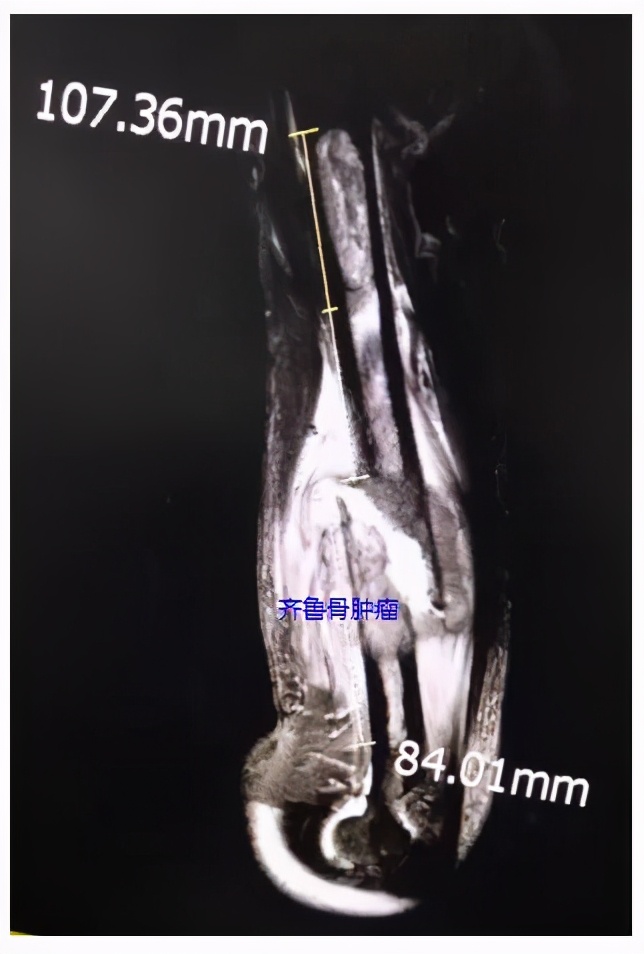

影像资料,红线示软组织包块边界

影像资料,髓内可见长节段病变,近端约108mm,远端约84mm